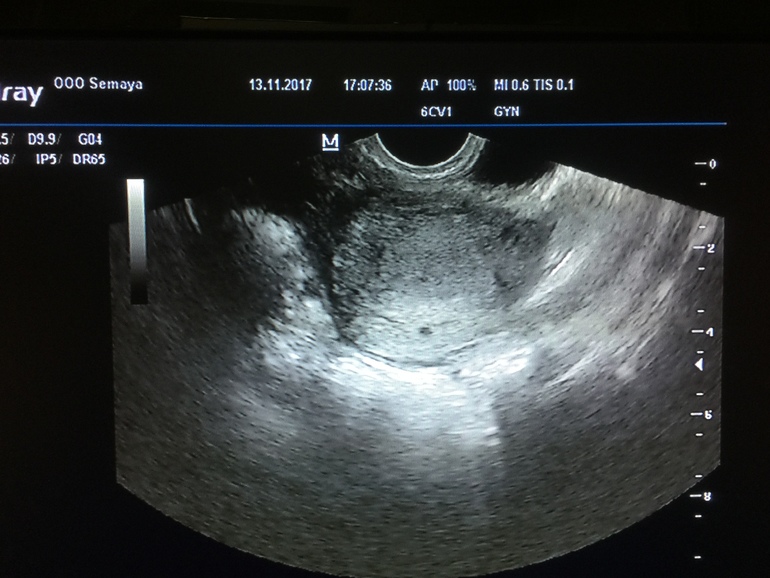

Вопросы о беременных и для беременных двойней Девчата, может ли бы это двойня? Срок 3-4 недели.. 2 кружочка

Девчата, может ли бы это двойня? Срок 3-4 недели.. 2 кружочка

Врач на узи ничего не сказал.

Ну может и два видится, я бы конечно ещё трёх вижу. Но врач бы наверное сказал, но надела всегда есть. Я когда пришла, мне сказали два пятнышка, но одно неправильной формы, врач даже его как вариант не хотела рассматривать, сказала рассосётся, но он не захотел рассасываться.